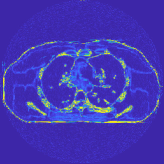

| views | ||||

|---|---|---|---|---|

| (a) , | (b) , | (c) , | (d) , |

III-B2 Algorithm Convergence Rate

Our main concern in convergence rates of Algorithm 1 lies with an inaccurate preconditioner (e.g., circulant one) particularly for the 3D sparse-view CT reconstructions. To see the effects of using a loose preconditioner in Algorithm 1, we compared the convergence rates of the 3D case with those of 2D (Fig. 5(a) and Fig. 5(b)). In the first iterations, Algorithm 1 converges faster in 2D experiments than 3D experiments. However, after iterations, the convergence rates of Algorithm 1 are similar in both 2D and 3D reconstructions. In addition, more PCG (with a circulant preconditioner) iterations does not significantly accelerate Algorithm 1 (see Fig 2). These empirically observations imply that, in the 3D sparse-view CT reconstructions, Algorithm 1 using a circulant preconditioner ( PCG iterations) is a reasonable choice.